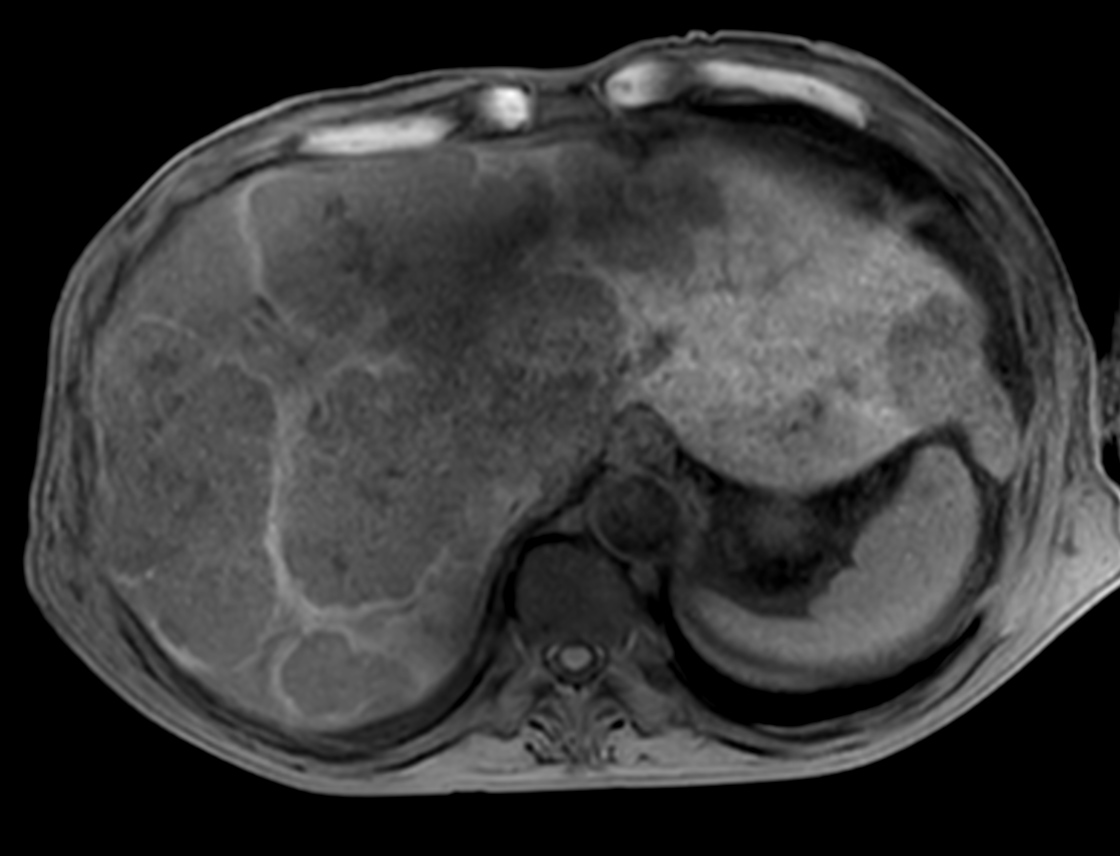

Patient with liver metastasis. The ExamCard includes techniques for efficient fat-free imaging over large field-of-views (mDIXON XD), a procedure for non-invasive liver fat quantification (mDIXON Quant), a multi-phase contrast-enhanced sequence (4D FreeBreathing) to improve imaging confidence and Compressed SENSE to accelerate the entire exam.

T2w TSE